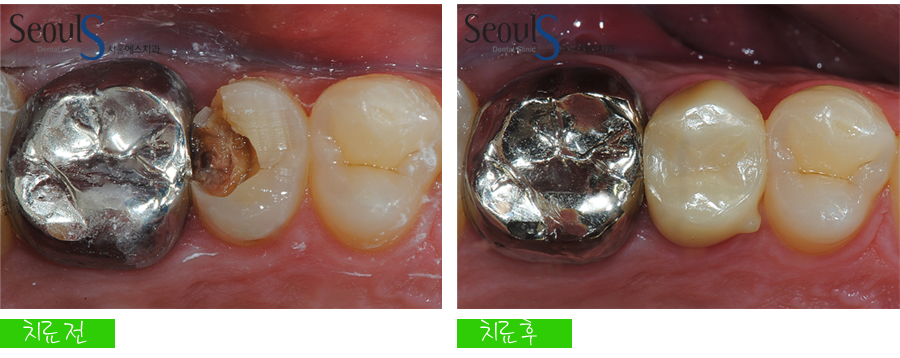

신경치료 후 크라운을 씌워 치료를 마친 모습입니다

예쁘고 튼튼하게 치료가 마무리 된 모습입니다

치료 전후 치아모습입니다

치아 충치가 신경까지 진행돼서

신경치료 후 크라운을 씌워서 치료를 마친 모습입니다